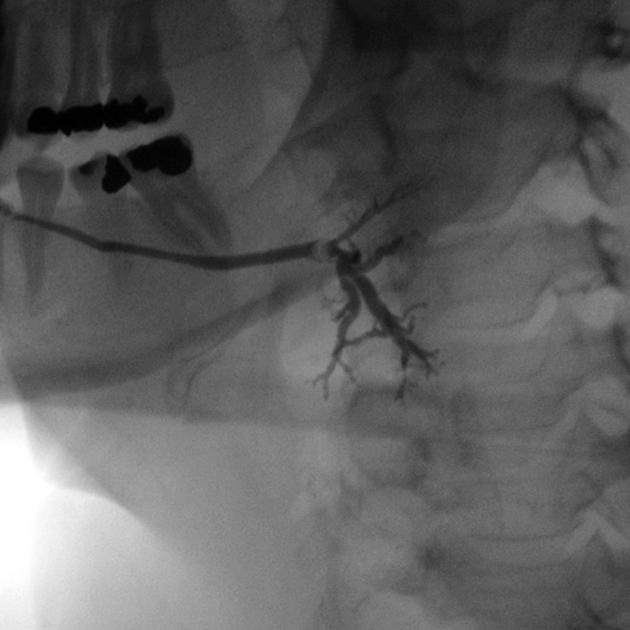

Sỏi tuyến nước bọt (Sialolithiasis)